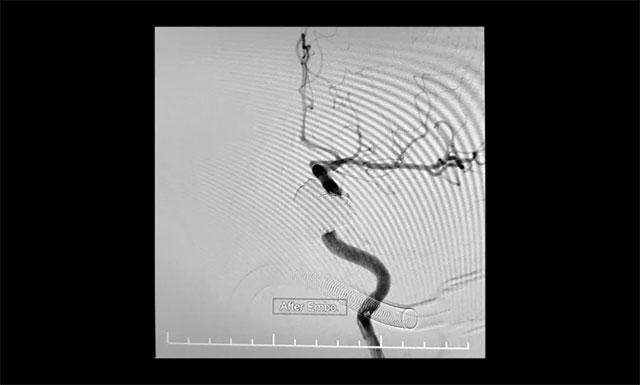

“钢筋混凝土技术”操作时需十分谨慎,若注胶不足会导致瘘口封闭不全症状不缓解,而注胶不慎又会导致胶溢入颈内动脉,造成颈动脉堵塞致大面积脑梗塞的灾难性后果。术中,张琪博士在李喆医生、周林华医生协助下先将海绵窦内小心填入13枚大直径弹簧圈作为“钢筋骨架”,然后准确地将球囊置于瘘口处的颈内动脉内,缓慢充盈球囊将瘘口暂时与颈内动脉隔离,然后小心翼翼地向瘘口内注入onyx胶封堵,并仔细观察胶的反流和扩散情况。该方法每次球囊阻断颈内动脉的时间不能超过6分钟,否则将可能导致脑缺血。“1分钟、2分钟、3分钟……”最终,经过几个循环的封堵,瘘口被栓塞得严严实实,在确认瘘口及主要异常回流途径完全闭塞后,及时终止手术,取得了较好的临床效果,术中造影证实瘘口均完全闭塞。

▲ 术中造影证实瘘口均完全闭塞